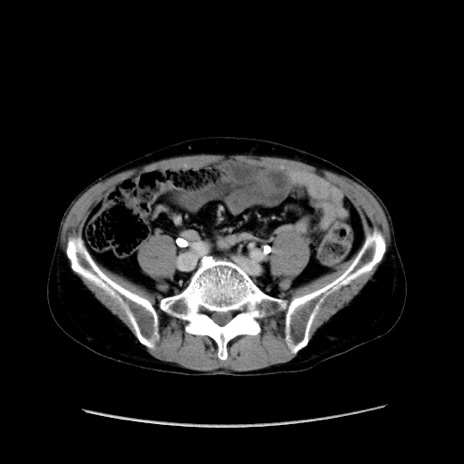

症例37(横断像)

【症例】40歳代 男性

【主訴】腹痛

【現病歴】4時間ほど前に電車に乗車中に臍部上より腹痛出現。徐々に増悪し起立困難となり、救急外来受診。生ものは数日食べていない。今朝お雑煮を食べた。

【身体所見】BT 36.8℃、BP 117/84mmHg、HR 91/min、SpO2 97%、苦悶様、腹部:臍上部広範囲圧痛あり、反跳痛±

【データ】WBC 8100、CRP 0.03